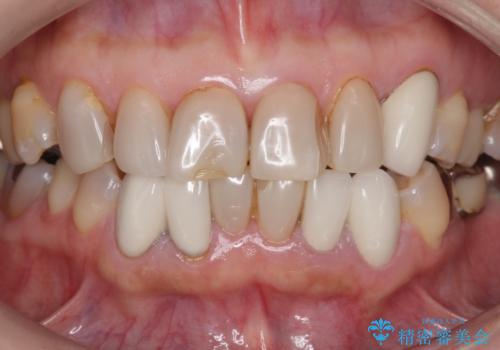

- 前歯の色や形を全体的に綺麗したいといらっしゃった方の症例です。

上顎は左側 4 番目から右側 4 番目までの 8 歯をオールセラミッククラウンで補綴しました。

下顎は左側 4 番目から右側 4 番目までの 8 歯と左下 567 ブリッジをオールセラミッククラウンで補綴し、右下67の銀歯はセラミックインレーによる修復を行いました。

今回用いたオールセラミッククラウンはジルコニアフレームという白い素材の上にセラミックを盛っているため、審美性が非常に高いのが特徴です。

また、ジルコニアは人工ダイヤモンドの材料にも使われているほど高い強度を持っており、そのためオールセラミッククラウンは審美性だけでなく、奥歯やブリッジの補綴も可能とするクラウンです。